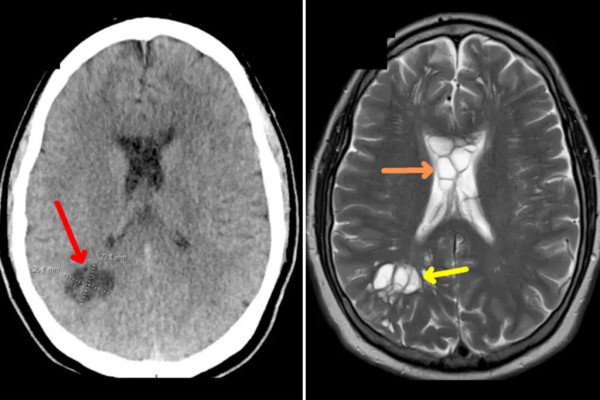

根據外媒報道,美國佛羅里達州一名52歲男子因長期出現偏頭痛而到醫院檢查經過醫生進行電腦斷層與核磁共振造影檢查後發現,男子的腦內多個腫脹的囊腫。其後經傳染病專家發現,男子的腦部遭受豬肉絛蟲寄生,甚至已經在內部產卵。

男子最後證實罹患寄生蟲感染神經囊蟲病,而他在服用抗寄生蟲及消炎等藥物後,病情已有所好轉。